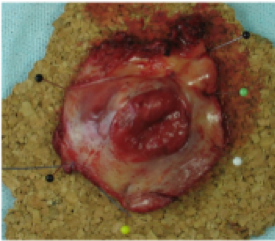

A.

B.

C.

Figur 1: Mindre excisionspreparat uppnålat på korkplatta (A), medelstort excisionspreparat uppnålat på korkplatta (B) och posterior partiell vulvektomi (C). Om vissa anatomiska strukturer eller resektionsränder är av intresse kan dessa med fördel markeras med särskild färg på nålen eller med tusch.